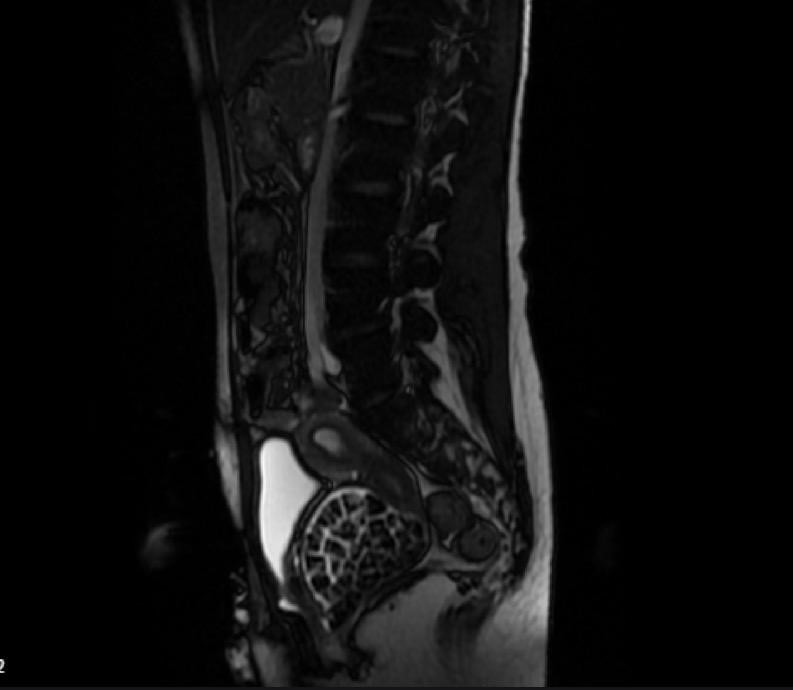

Hastasının durumunu değerlendiren Üroloji Uzmanı Doç. Dr. Erkan Erkan, "Hastamızın 2004 yılında doğduğunu ardından doğar doğmaz ekstrofi vezika dediğimiz 50 binde bir görülen bir anomaliden dolayı art arda ameliyatlar geçirdiğini öğrendik. 10 yaşında yine bir ameliyat geçirmişti, gerekli görüntüleme ve tetkiklerimizi yaptırdık. Normalde mesanesinin olması gereken yerin hemen arka kısmında taşlarla dolu bir kese olduğunu gördük, bunun üzerine ek görüntülemeler; MR çektirdik. Hastamız çelişkili açıklamalar almıştı, kendi radyolojik kliniğimiz ve edindiğimiz konsültasyonlarda taşların mesanede değil vajinal boşlukta oluştuğunu düşündük, bir planlama yaptık.

Genç kızın uzun süredir karın ağrısı çektiğini belirten Jinekolojik Onkoloji Uzmanı Op. Dr. Emin Erhan Dönmez, "Mesane taşları olduğu düşünülerek daha büyük bir hastaneye refere edilmiş. Aramızda mini bir konsey yaparak muayene ettik. Vajen bir hazne görevi görerek orada durağan bir idrar, uzun süre beklediği için idrar içindeki minerallerde çökerek taşlar oluşmuş. Mesanedeki idrarın vajene akmış olabileceği ve vajende göllenen idrar nedeniyle taşların burada oluşacağını düşündük, ameliyatımızı planladık. Ameliyata tanı amaçlı girmiştik, sistoskopi (Mesane gibi idrar yollarını kapsayan kısımlardaki rahatsızlıkların teşhis ve tedavisinde kullanılan endoskopik bir yöntem) dediğimiz ameliyatı Erkan Hocam ile birlikte gerçekleştirdik.

Önce mesaneyi bir görüntüledik, mesane tabanına yaklaşık 2-3 cm’lik bir alandan vajene fistülize olduğunu gördük. Mesaneden vajene geçtiğimiz esnada tüm vajenin taşlarla dolu olduğunu gördük. Tanı amacıyla girdiğimiz ameliyatta her şey de olağan gittiği için tedaviye geçtik. Taşların çıkabileceği kadar bir genişlik sağladık. Daha sonra yaklaşık en büyüğü 2,5 cm boyutlarında olan, irili ufaklı 287 tane taşı ameliyat esnasında çıkarmış olduk. Taşların tekrarlamaması için idrarın göllenmemesi, en azından dışarıya rahatça boşalabilmesi için vajinal rekonstrüksiyonu sağladık. Ameliyatta da herhangi bir problem yaşamadık. Literatürü Erkan Hocam ile birlikte değerlendirmiştik. Primer olarak vajende birikmiş olan bu kadar çok sayıda taşla ilgili bir makale görmedik, rastlamadık" dedi.